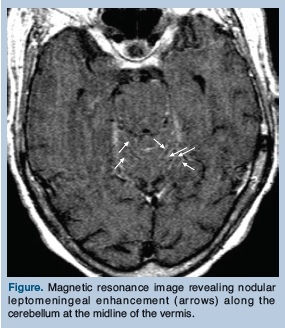

The patient’s tuberculin skin test revealed a 16-mm induration. By report, the patient had no known history of TB, and it was unclear whether she had ever received the Bacille Calmette-Guérin (BCG) vaccine. Magnetic resonance imaging (MRI) of the brain demonstrated nodular leptomeningeal enhancement along the cerebellum at the midline of the vermis (Figure). Based on the CSF and MRI findings, a presumptive diagnosis of TB meningitis was made, and the patient was immediately started on the following daily medications: isoniazid, 300 mg; levofloxacin, 750 mg; pyrazinamide, 1500 mg; rifampin, 600 mg; and dexamethasone, 12 mg. Levofloxacin was chosen instead of ethambutol because of its better CSF penetration, better side-effect profile, and a lower likelihood of the patient’s TB being resistant to levofloxacin based on the pulmonary consult recommendations, although the pharmacologic literature on the best drug regimen to overcome drug resistance in TB meningitis is conflicting.